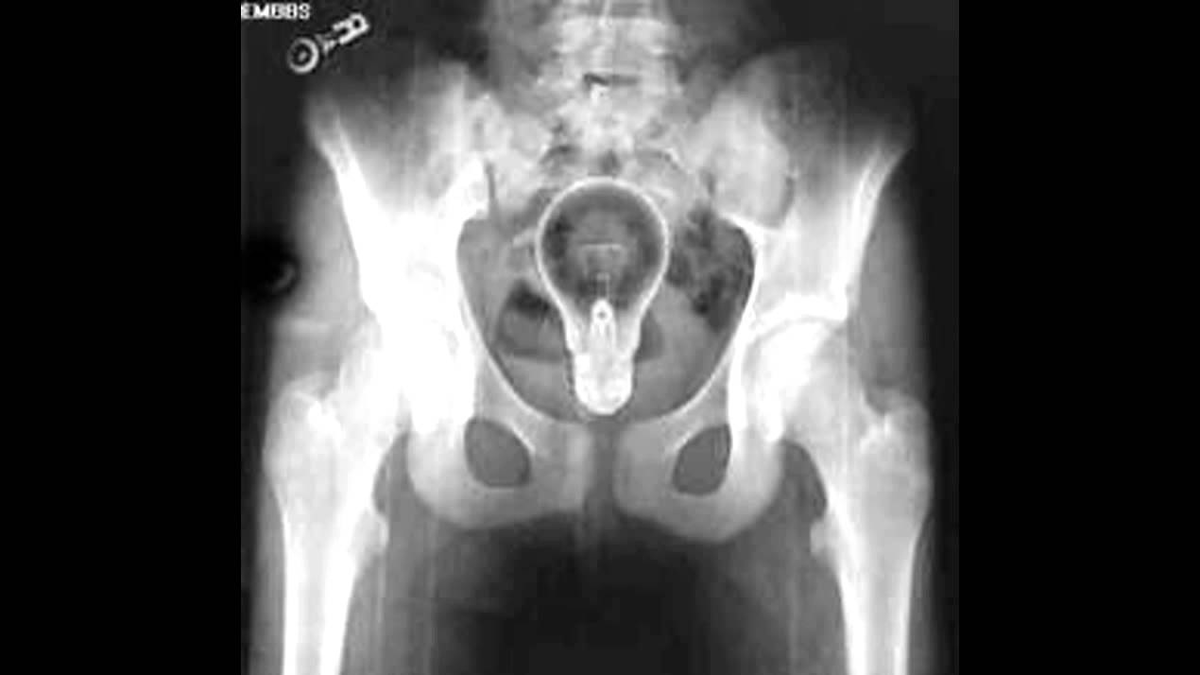

Лампочка

Однажды в отделение поступил очень старый дедушка. Из его прямой кишки извлекли самую настоящую лампочку! Врачам он признался в том, что пытался так излечить долго мучавший его геморрой. Он вставил разогретую лампочку в прямую кишку, но достать ее не смог.